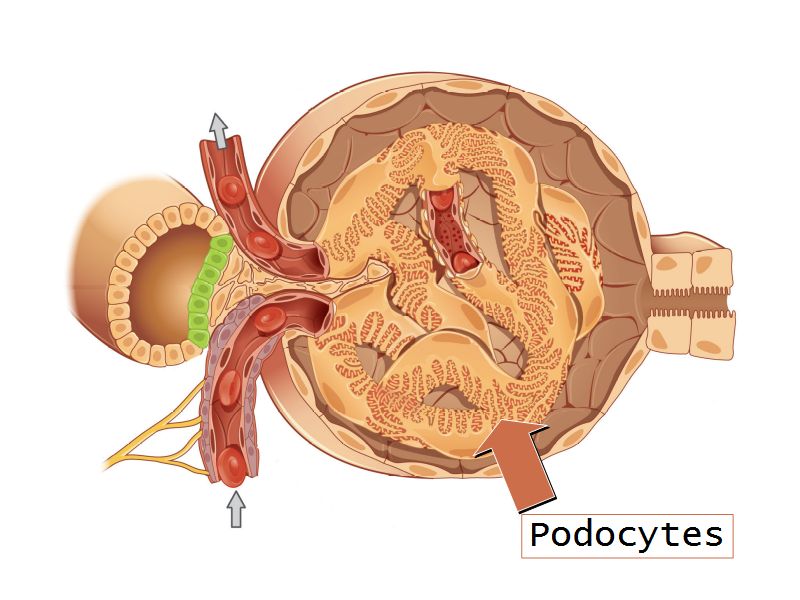

Podocytes

- Visceral layer of epithelium

- Protrude into capsular space

- Attached to basement membrane

- Long cytoplasmic extensions

- Primary processes

- Secondary processes

- Podocyte feet

- Tightly spaced

- Filtration slits 20 - 30 nm wide